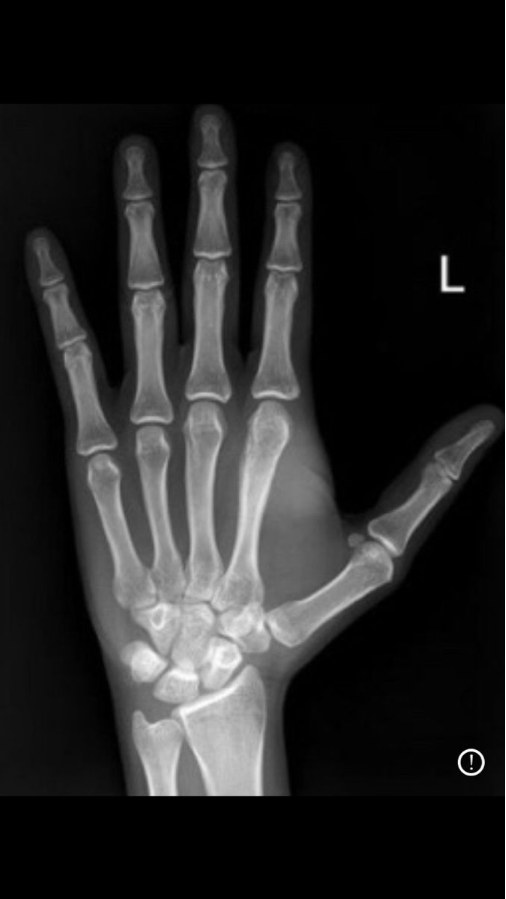

Left Hand X-Ray AP

A Left Hand X-Ray is a quick and painless imaging test used to examine the bones, joints, and soft tissue structures of the left hand. It helps diagnose fractures, dislocations, swelling, arthritis, infections, and injuries caused by falls, sports accidents, or pain.

This test provides clear images of the fingers, palm, wrist area, and hand bones for accurate diagnosis and treatment planning.

A Left Hand X-Ray uses a small amount of radiation to capture detailed images of the bones in the left hand. It is commonly recommended for pain, injury, reduced movement, or suspected fractures.

Left Hand X-Ray Normal

A normal Left Hand X-Ray shows healthy bone alignment, no fractures, no dislocation, and normal joint spaces. If pain continues despite a normal X-ray, your doctor may advise further evaluation.

Broken Left Hand X-Ray

A broken Left Hand X-Ray may show cracks, fractures, displaced bones, or swelling around the injured area. Immediate diagnosis helps in proper treatment such as plaster, splint, or orthopedic care.